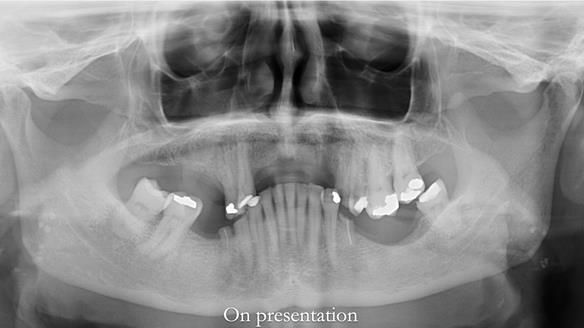

Keith’s case was one of the most challenging and rewarding cases I’ve treated this year. This 64 year old man presented with ill-fitting acrylic partial dentures that lacked stability, retention, and aesthetics. They constantly broke. He had lost the upper front teeth in a road traffic accident in his early 20s. The unopposed teeth had erupted, taking up space. After careful planning, we made a durable, metal-based upper partial denture/splint to address his dental concerns. He loved the outcome.

1. Denture design: A custom cobalt-chromium framework was Scandinavian-designed to maximise stability, protect the remaining teeth, and allow for future additions if needed.

2. Onlay preparations: Composite onlays were fitted for his upper left premolars to repair these teeth and support the new denture.

Keith’s denture incorporated a Duracetal shell clasp on upper right first premolar (Myerson), which are designed to be virtually visible, providing a more aesthetic solution while enhancing patient comfort. The Scandinavian-inspired approach, based in modern removable prosthodontic techniques, ensured the denture was not only durable but also visually pleasing. Additionally, the design was carefully planned to allow for future modifications, ensuring that if Keith loses additional teeth, the denture can be adapted rather than replaced entirely.

I also used the Dahl concept to re-establish the occlusion upon fitting the RPD, which helped to intrude the lower left canine without needing to grind it too much.